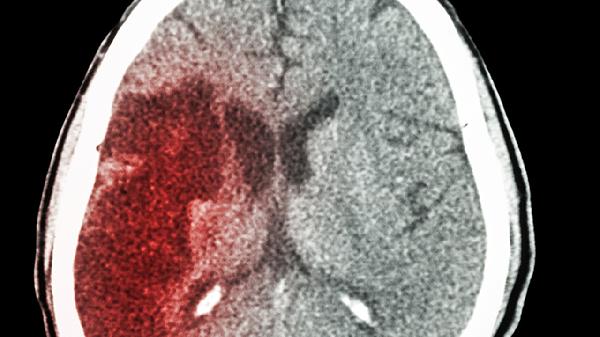

脑梗预警:两项关键检查不可少,早发现早治疗,康复事半功倍

脑梗就像身体里的“定时炸.弹”,发作前往往悄无声息。很多人以为只有老年人才需要担心,实际上近年来40岁以下的发病案例增加了近三成。别等到突然嘴歪眼斜才后悔,这两项关键检查能帮你提前拆弹!